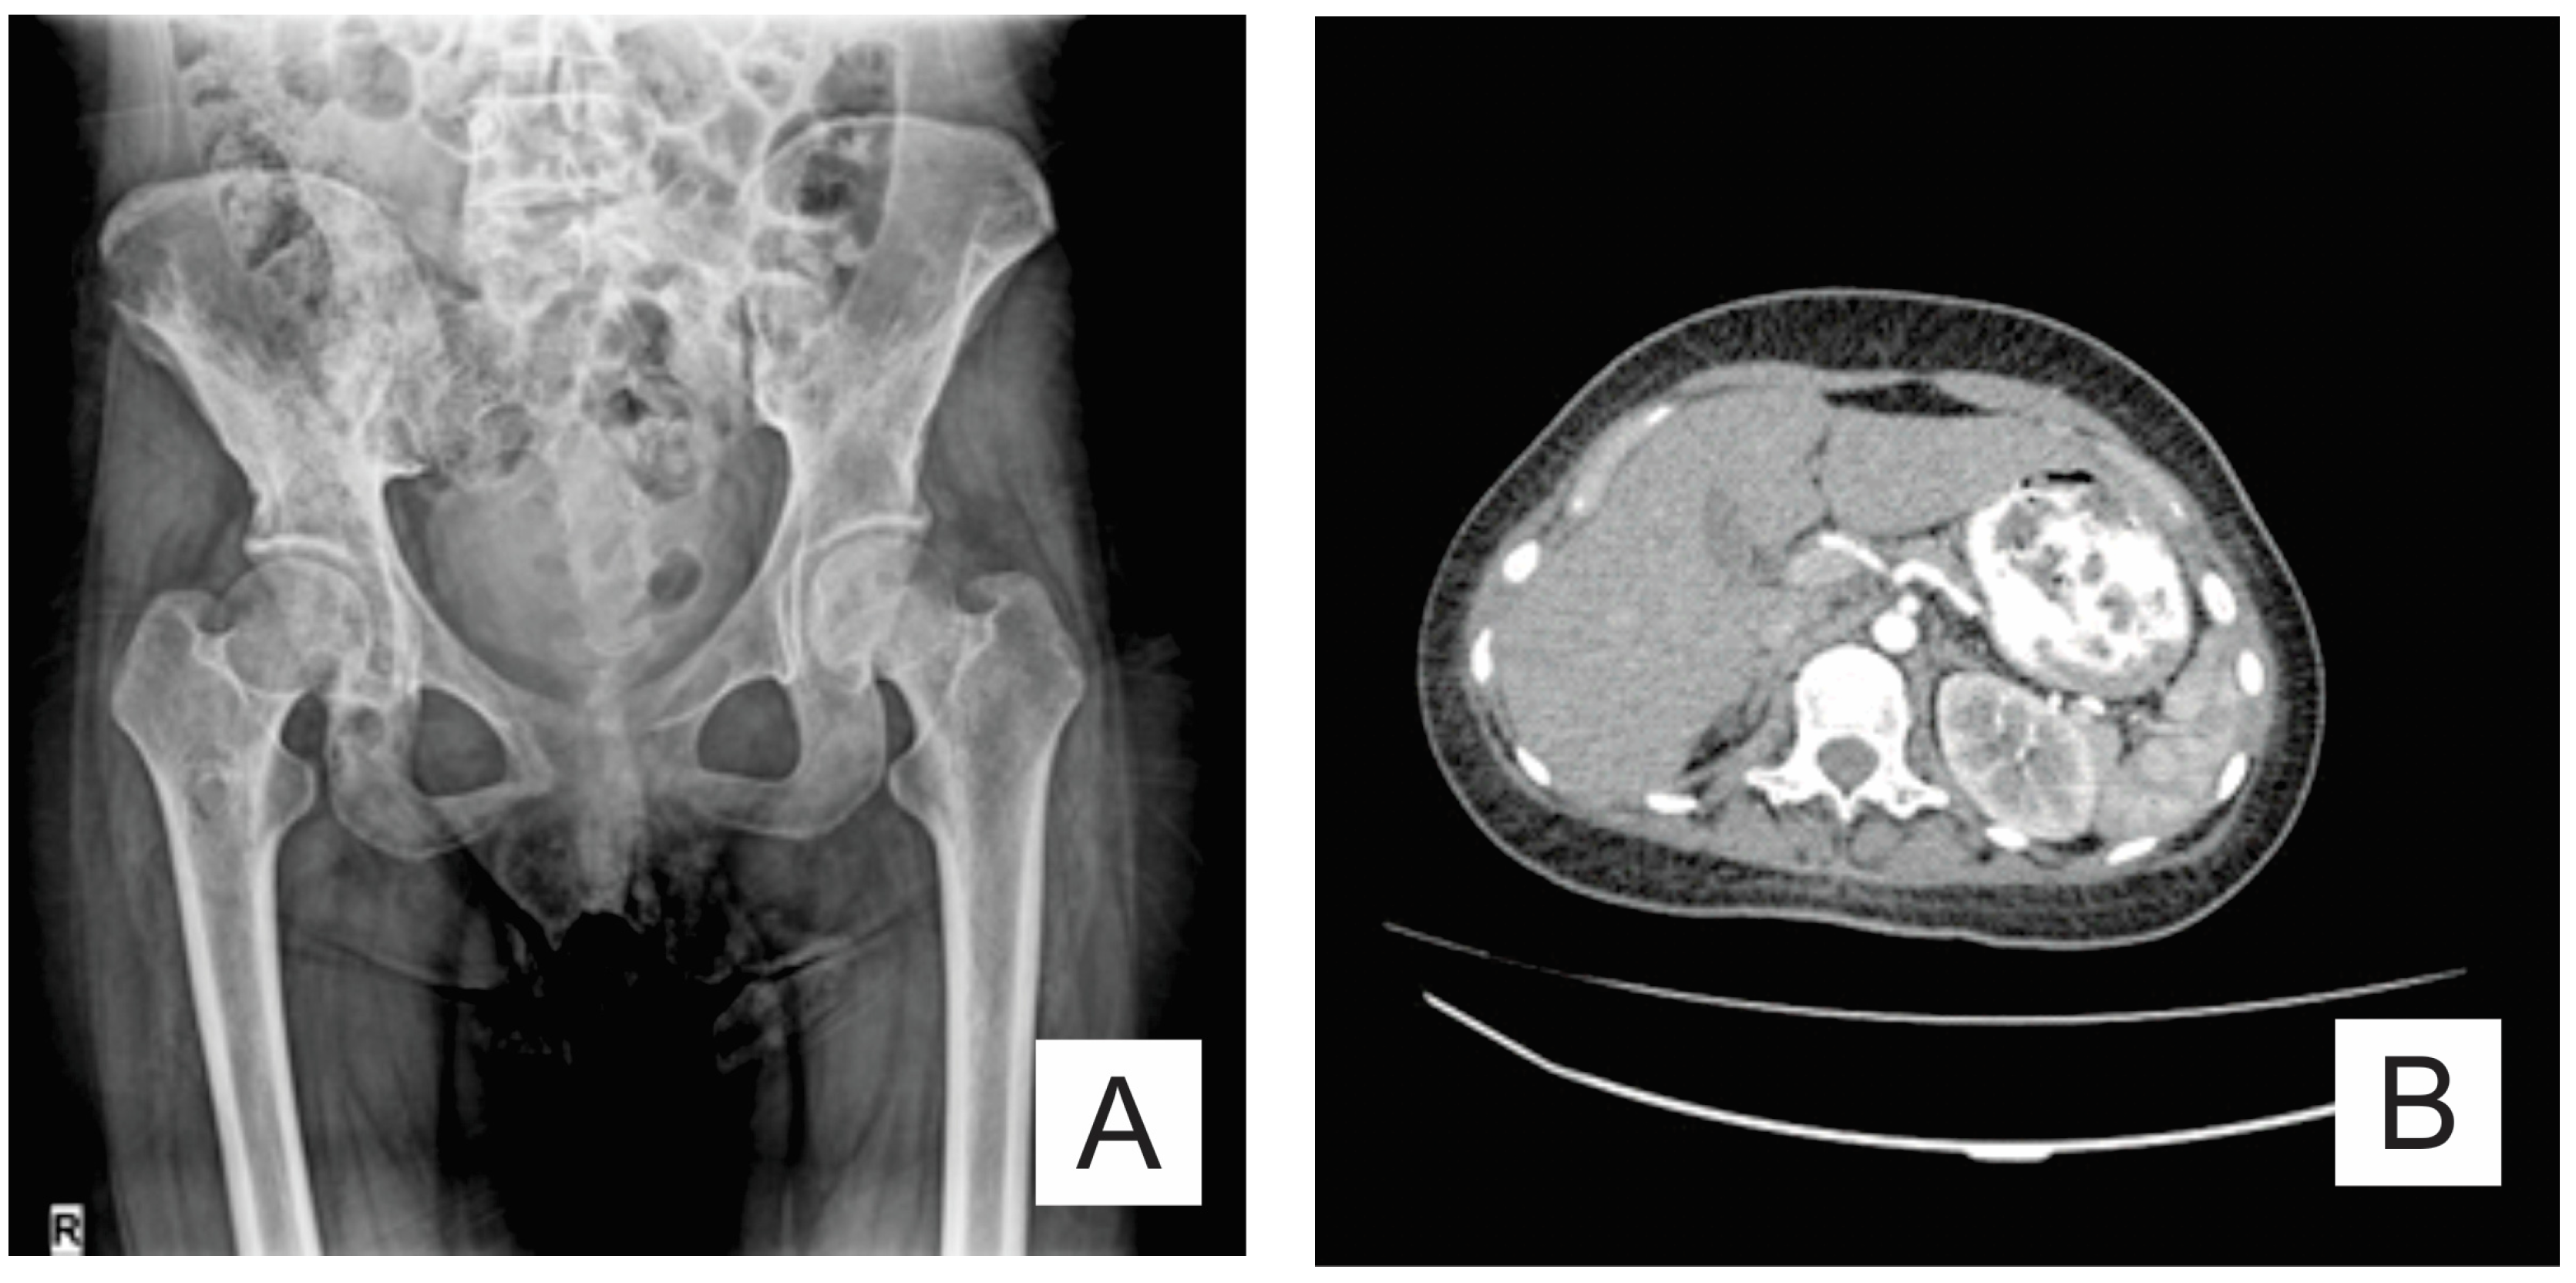

| Month I | C7 corpectomy and reconstruction with autologous graft from the iliac crest, macroscopic resection of the posterior arches C7-T1 and fixation with C4-C5-T3-T4 cervico-thoracic hybrid system |

| Month III | Ablation of osteosynthesis material and bone graft and T1 corpectomy, reconstruction with C6-T1 mesh fixed with proximal and distal screw |

| Month IX | Ablation of damaged osteosynthesis material mesh C6-T1, ablation of thoracic screws, and introduction of bilateral T3, T4, and T5 screws |